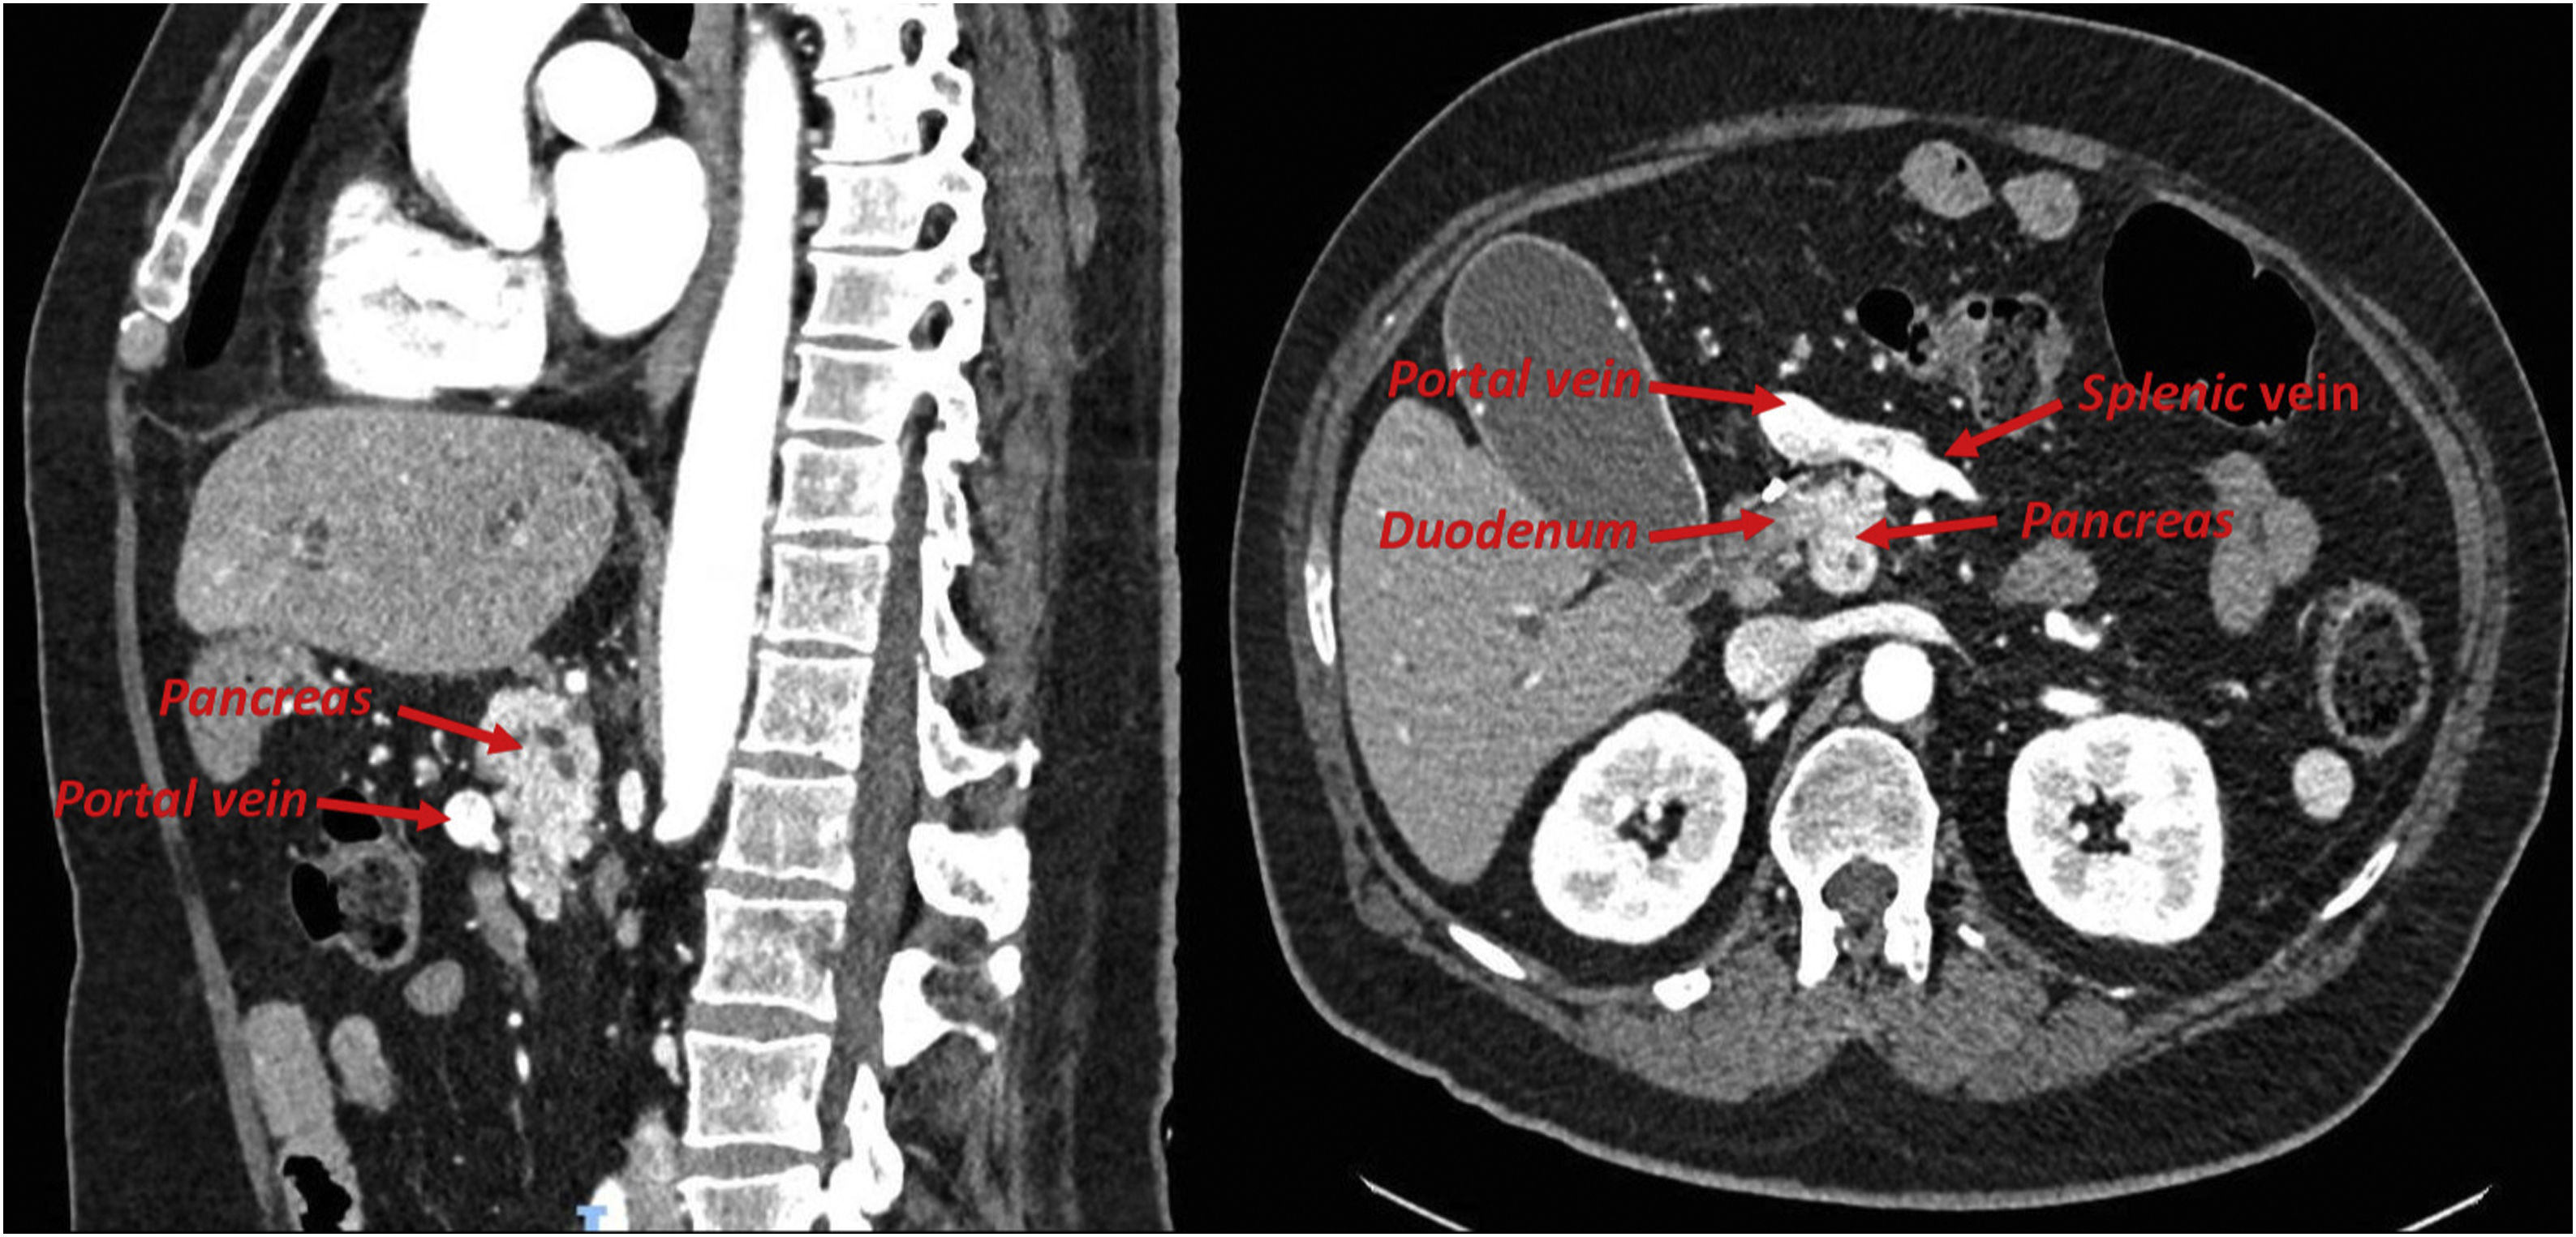

A 64-year-old male with history of SADI-S bypass was admitted due to jaundice, constitutional syndrome and hyperbilirubinemia. Abdominal CT scan showed bile ducts dilation due to a resectable pancreatic head adenocarcinoma and an incidental finding of a preduodenal portal vein (Fig. 1), an extremely rare anatomical variant with about 100 cases described worldwide.

Cephalic duodenopancreatectomy was performed with double-loop reconstruction and pancreatico-jejunal anastomosis without incidents. Preduodenal spleno-porto-mesenteric confluence was observed (Fig. 2). The biliopancreatic limb of SADI-S was used as biliopancreatic limb in double-loop reconstruction. The postoperative period was uncomplicated, and the patient was discharged with nutritional follow-up and exocrine pancreatic support.